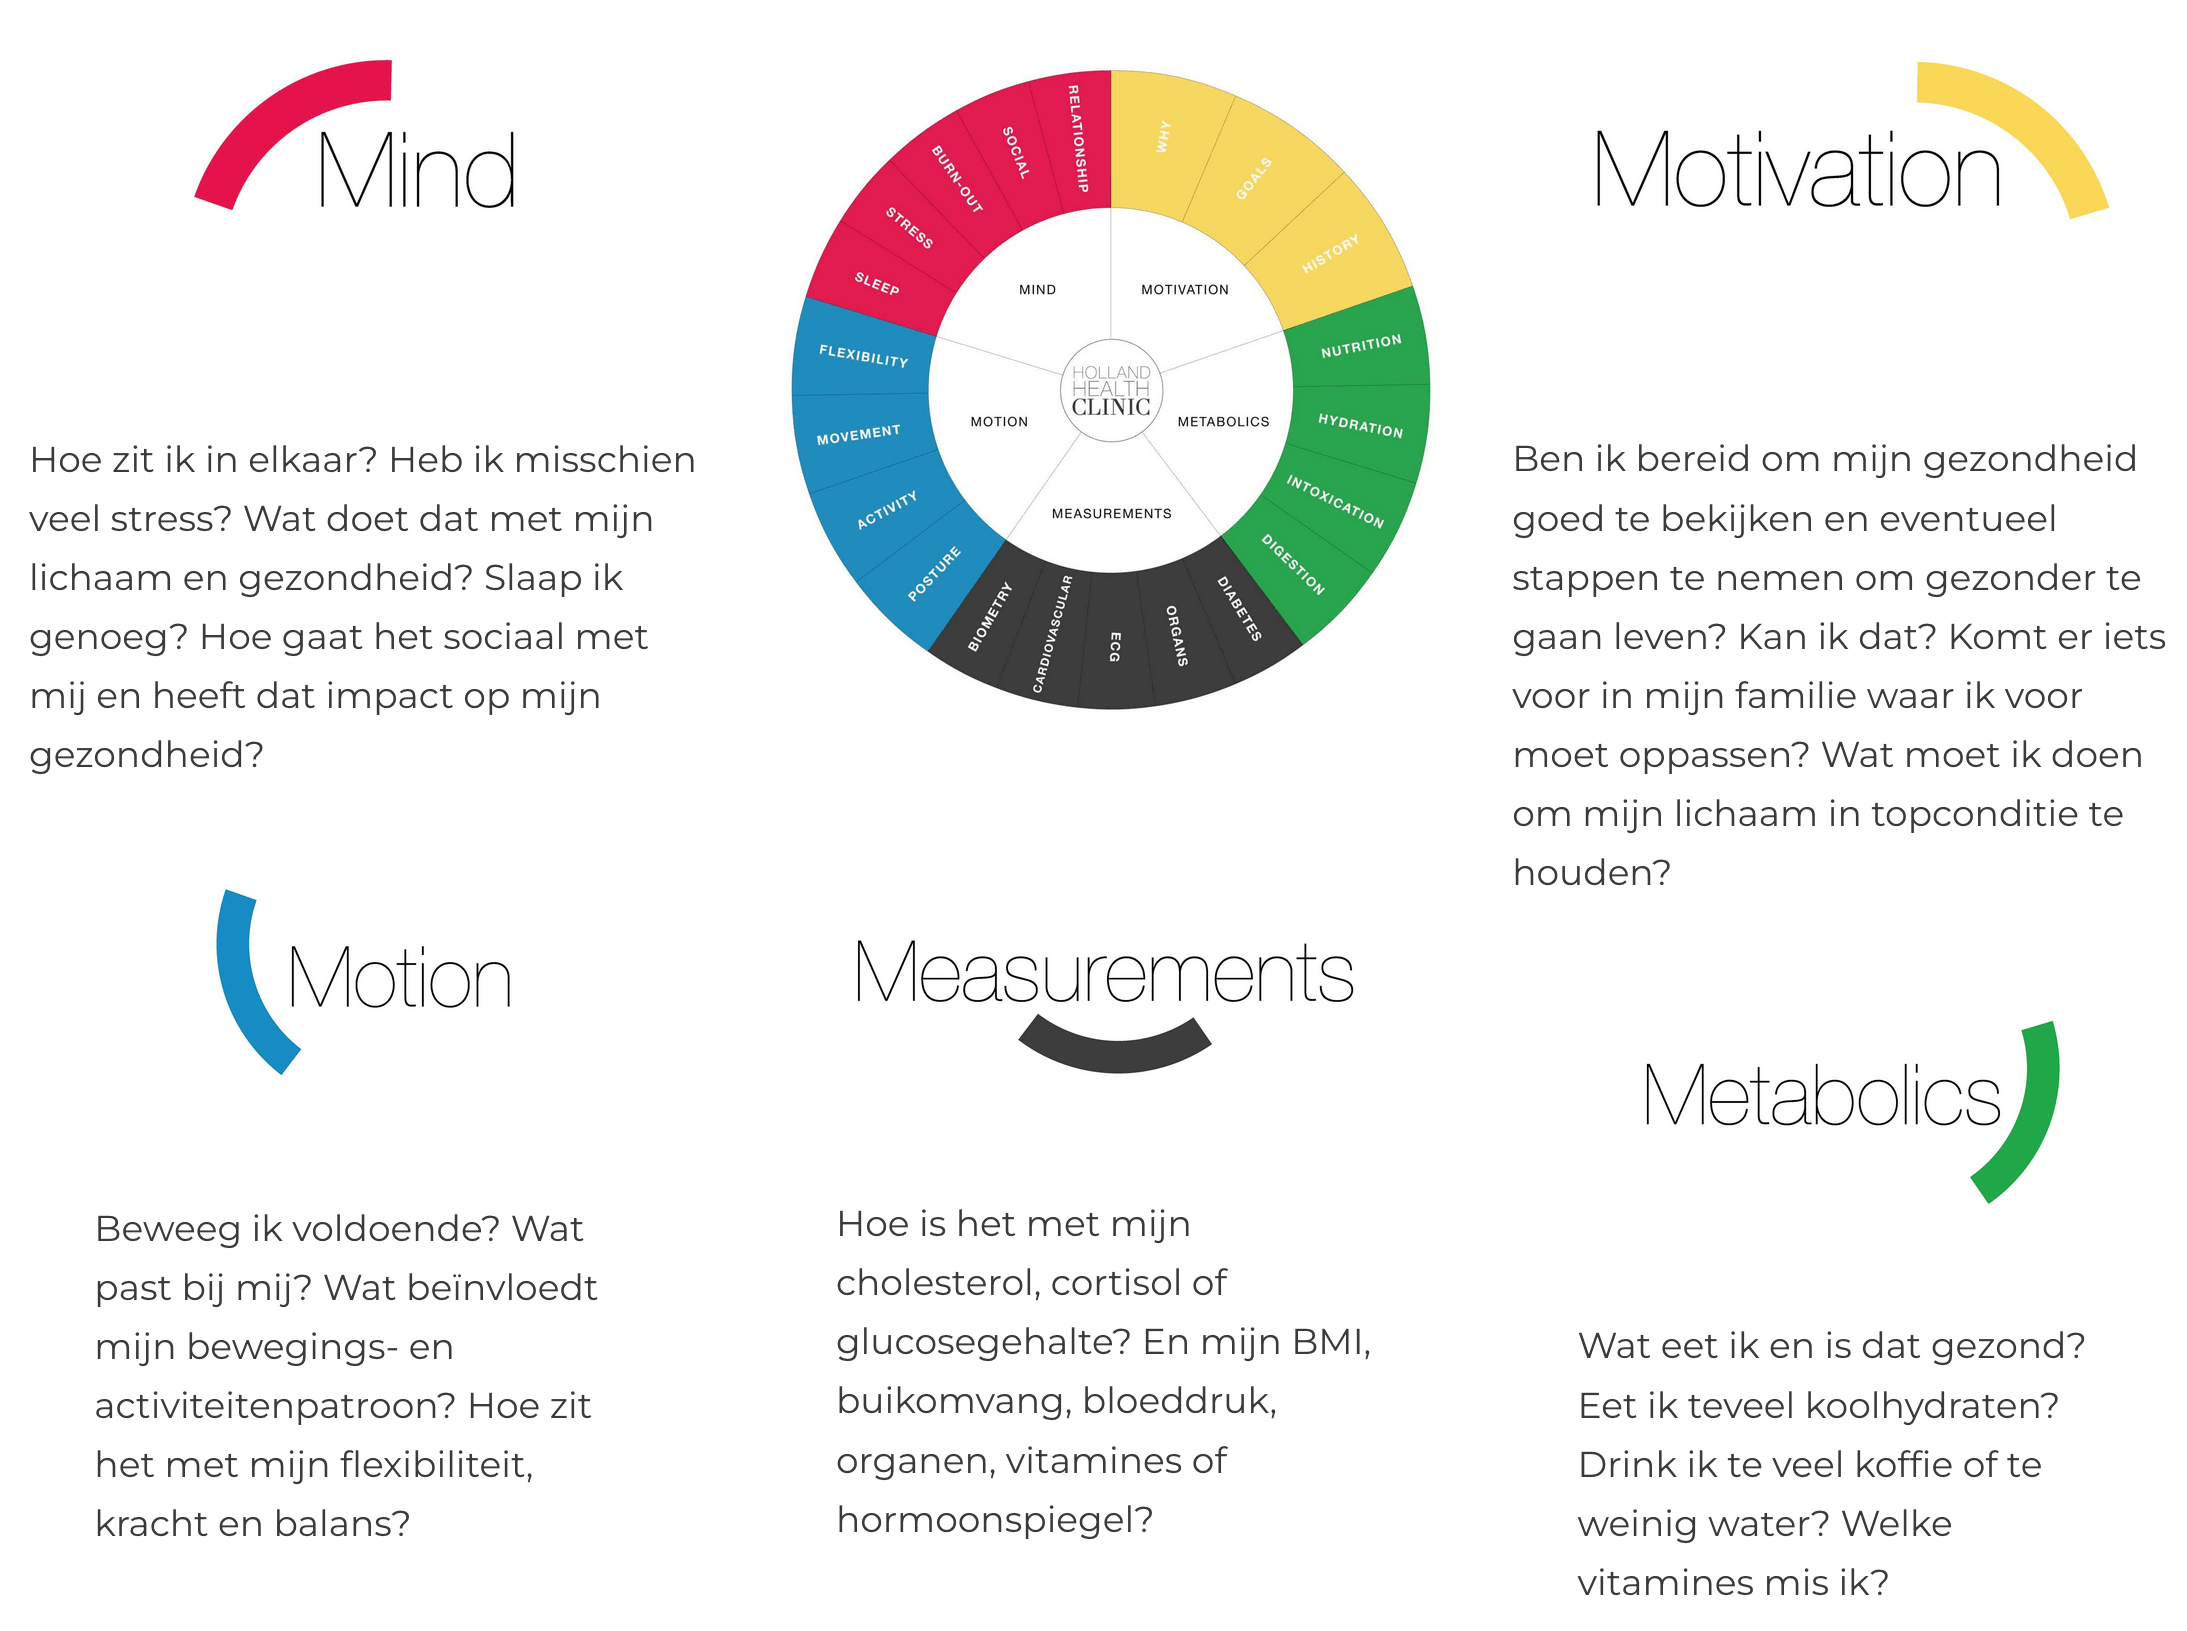

Omdat je met kennis, inzicht en aandacht grip op je gezondheid kan krijgen. En dat is in deze drukke maatschappij geen overbodige luxe. Omdat ook een veranderende levensfase zoals de overgang heel veel klachten kan geven. We luisteren, nemen de tijd en hebben de aandacht voor jou tijdens de checks. We brengen jouw ‘puzzelstukjes’ in kaart en analyseren jouw data. Bij AAYA doen we meer dan alleen bloedprikken, en dit is anders dan bij andere Health Checks. We beschikken over de juiste medische kennis en hebben een brede kijk (360 graden) op jouw gezondheid met behulp van onze 5 M’s (mind, motivation, motion, measurements, metabolics).

- Leefstijl vragenlijsten Motivation, Mind, Motion, Metabolics

- Uitgebreide AAYA vragenlijst om inzicht te krijgen in jouw leefstijl, slaap- en leefpatroon (Motivation, Mind, Motion, Metabolics)